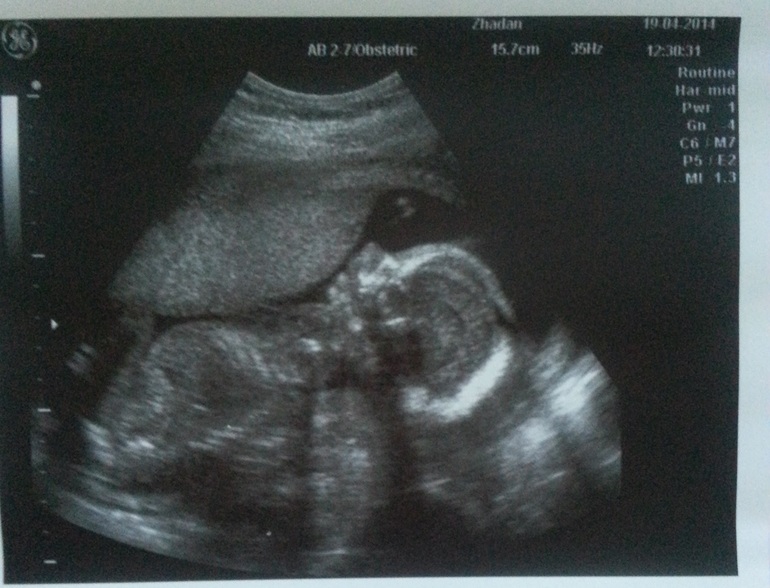

Анализы и показатели УЗИ в 20 недель беременности

Теперь навещать женскую консультацию потребуется дважды в месяц. Обязательным будет скрининговое ультразвуковое исследование (УЗИ). Оно дает наиболее исчерпывающую информацию. Главные задачи:

- оценка состояния плаценты;

- обследование почек, печени, желудка, легких и прочих внутренних органов ребеночка;

- анализ количества вод, окружающих плод (т.н. околоплодные воды).

Очень тщательно изучается сердце, чтобы исключить развитие пороков.

На данном этапе гинеколог может назначить УЗИ и анализы крови и мочи: первый делается для контроля уровня гемоглобина и глюкозы, а второй — чтобы определить, как работают почки.

Ультразвуковое исследование проводится с 18-й по 24-ю неделю и является многопрофильным. Врач определяет, насколько размеры всех органов плода соответствуют нормам и как они функционируют. Также на 20-й неделе беременности измеряется длина шейки матки, количество амниотической жидкости, уточняется расположение плаценты. При необходимости параллельно с УЗИ назначается тройной тест крови на определение пороков развития.

узи плода на 20 неделе

Акушерство и гинекология Диагностика УЗИ Узи плода 20 неделяСтоимость узи во втором триместре в сроке от 14 до 26 недель составляет 550 гривен. В цену включено проведение пренатального скрининга, биометрии по протоколам, 3D/4D визуализация. Стоимость комплексного пренатального скрининга по PRISCA (УЗИ + свободный эстриол + альфа-фетопротеин + бетаХГЧ с расчетом индивидуального риска хромосомных патологий (например синдрома Дауна или Эдвардса) и дефектов развития (например дефект нервной трубки) – 1060 гривен.

УЗИ плода в 20 недель беременности проводится рутинно в комплексе пренатальной диагностики.

В этот период акушер-гинеколог, проводящий УЗИ при беременности, может достаточно точно определить пол ребенка, вы сами сможете в этом удостовериться!

Ваш ребенок активно растет. При УЗИ плода в 20 недель беременности его длина составляет 19-20 см, а вес — около 400 граммов. При этом плоду еще достаточно места в его жилище, он свободно двигается, поворачивается, что можно увидеть при УЗИ плода в 20 недель беременности.

Информативным будет 3d 4d УЗИ плода при беременности, на котором доступны для просмотра лицевые структуры, спина, голова и т.д.

При проведении обычного УЗИ производятся измерения основных размеров плода для диагностики нормальных темпов развития.

Фетометрия (размеры плода) при УЗИ плода в 20 недель беременности в норме

- БПР (бипариетальный размер составляет 43-53 мм.

- ЛЗ (лобно-затылочный размер) 56-68 мм.

- ОГ (окружность головки плода) 154-186 мм.

- ОЖ (окружность живота плода) составляет 102 мм 124 -164 мм.

Нормальные размеры длинных костей при УЗИ плода в 20 недель беременности

- Бедренная кость 29-37 мм

- Плечевая кость 26-34 мм

- Кости предплечья 22-29 мм

- Кости голени 26-34 мм

Внутренние органы при УЗИ плода в 20 недель беременности обязательно изучаются.

Видны почки плода, исключается расширение лоханок (пиелоэктазия, гидронефроз) у плода, желудок, желчный пузырь, мочевой пузырь, кишечник, печень, легкие, сердце. При исследовании сердца при УЗИ плода в 20 недель беременности определяется правильность положения этого органа, симметричность камер сердца, целостность перегородок, правильность выхода магистральных сосудов. При наличии несоответствия норме, беременная направляется на специализированное УЗИ сердца плода, так как пороки сердца относятся к самым распространенным порокам развития плода. Диагностика порока сердца важно для определения прогнозов для жизни после родов. Иногда требуется проведение операции в первые часы жизни ребенка.